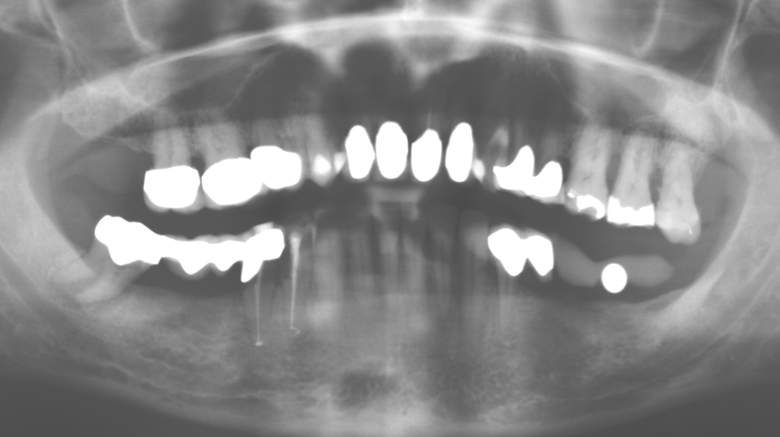

Fig. 1: Panoramic radiograph of initial situation in 2004.

A 52-year-old patient presented in our clinic for the first time in 2004 following tooth loss in the third quadrant, expressing a desire for a new prosthetic restoration. Periodontal and radiological diagnostics revealed the need for extensive periodontological treatment. In addition, teeth 48, 28 and 27 were attributed a very poor prognosis and were subsequently extracted (Fig. 1). Following the successfully completed, systematic periodontological treatment, a fixed dental implant was inserted with the introduction of five implants in tooth regions 35, 36, 37, 46 and 47. Prosthetic treatment of the natural teeth was effected with veneered zirconium dioxide ceramic crowns; the implants were composed of two-piece, individual zirconium dioxide abutments and similarly veneered crowns made of a zirconium dioxide ceramic (Cercon base colored, Dentsply Sirona Lab). Definitive insertion of the prosthetic restoration occurred in 2005.